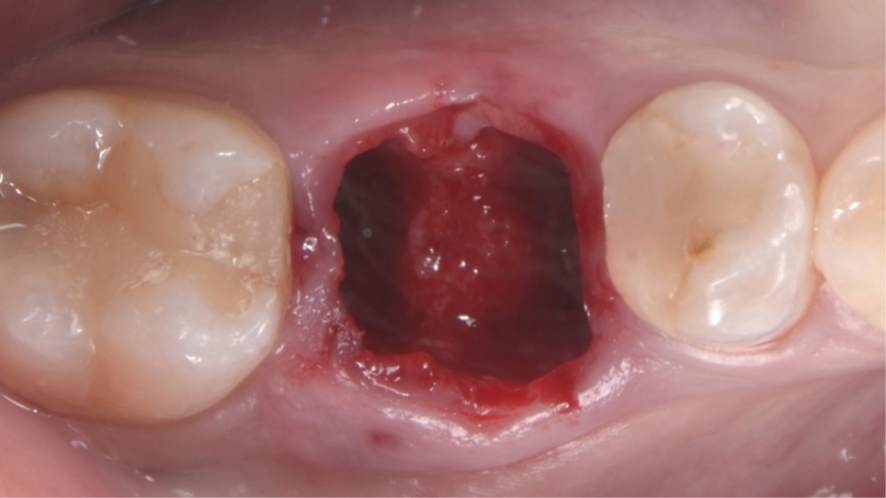

Mulher de 48 anos, sem antecedentes médicos relevantes, procurou atendimento odontológico com queixa principal de dor contínua em região do primeiro molar inferior direito. Na avaliação clínica foi observado uma fístula na vestibular do dente 46 (Figura 1) e a tomografia revelou uma fratura longitudinal, comprometendo a manutenção deste dente (Figura 2). Confirmada a necessidade de exodontia, foi planejada a instalação de um implante imediato e a confecção de um cicatrizador personalizado diretamente na plataforma do implante com um pilar provisório de titânio. Foi realizada uma extração dentária minimamente traumática visando preservar a integridade dos tecidos moles e duros circundantes (Figuras 3 e 4).